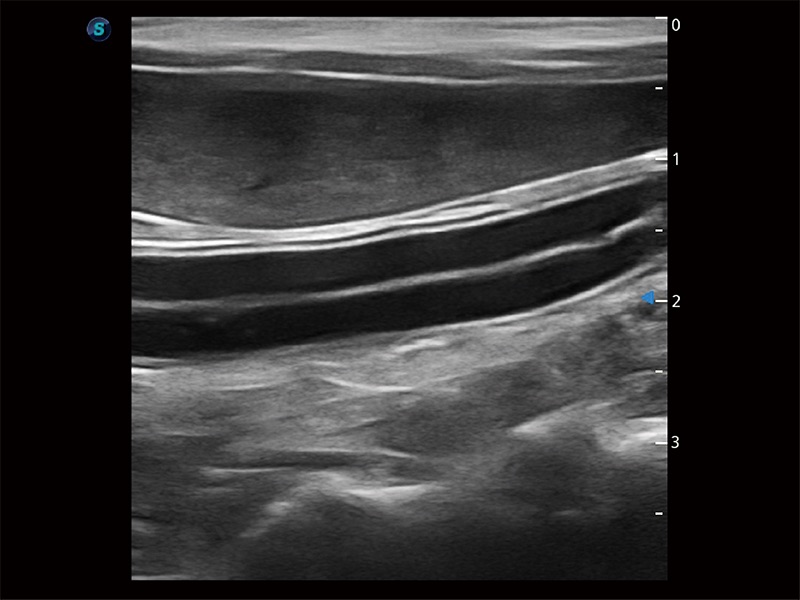

高性能和先进的临床应用工具可以为动物医生提供临床信心。ProPet 80 搭载了先进的腹部和浅表应用工具,帮助医生在日常临床实践中发挥前所未有的作用。

操作简便,无需高频度外力作用即可真实反映组织的形变,快速评估肿瘤良恶性。

为精细结构及组织边缘提供高清晰度的图像和更大的成像视野。帮助减轻医生的用眼疲劳,快速精准获得测量的数据。